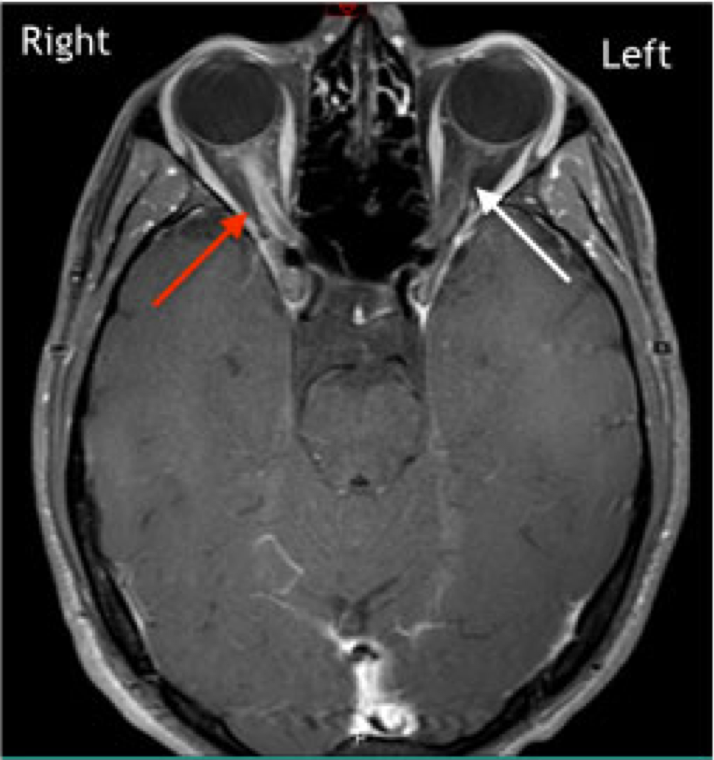

Visuais

- Perda visual com dor ocular

- Visão dupla

- Dificuldade de visão para cores (Discromatopsia)

- Sintoma inicial comum

Exames de Imagem

incluir as imagens e as caracteristicas de em